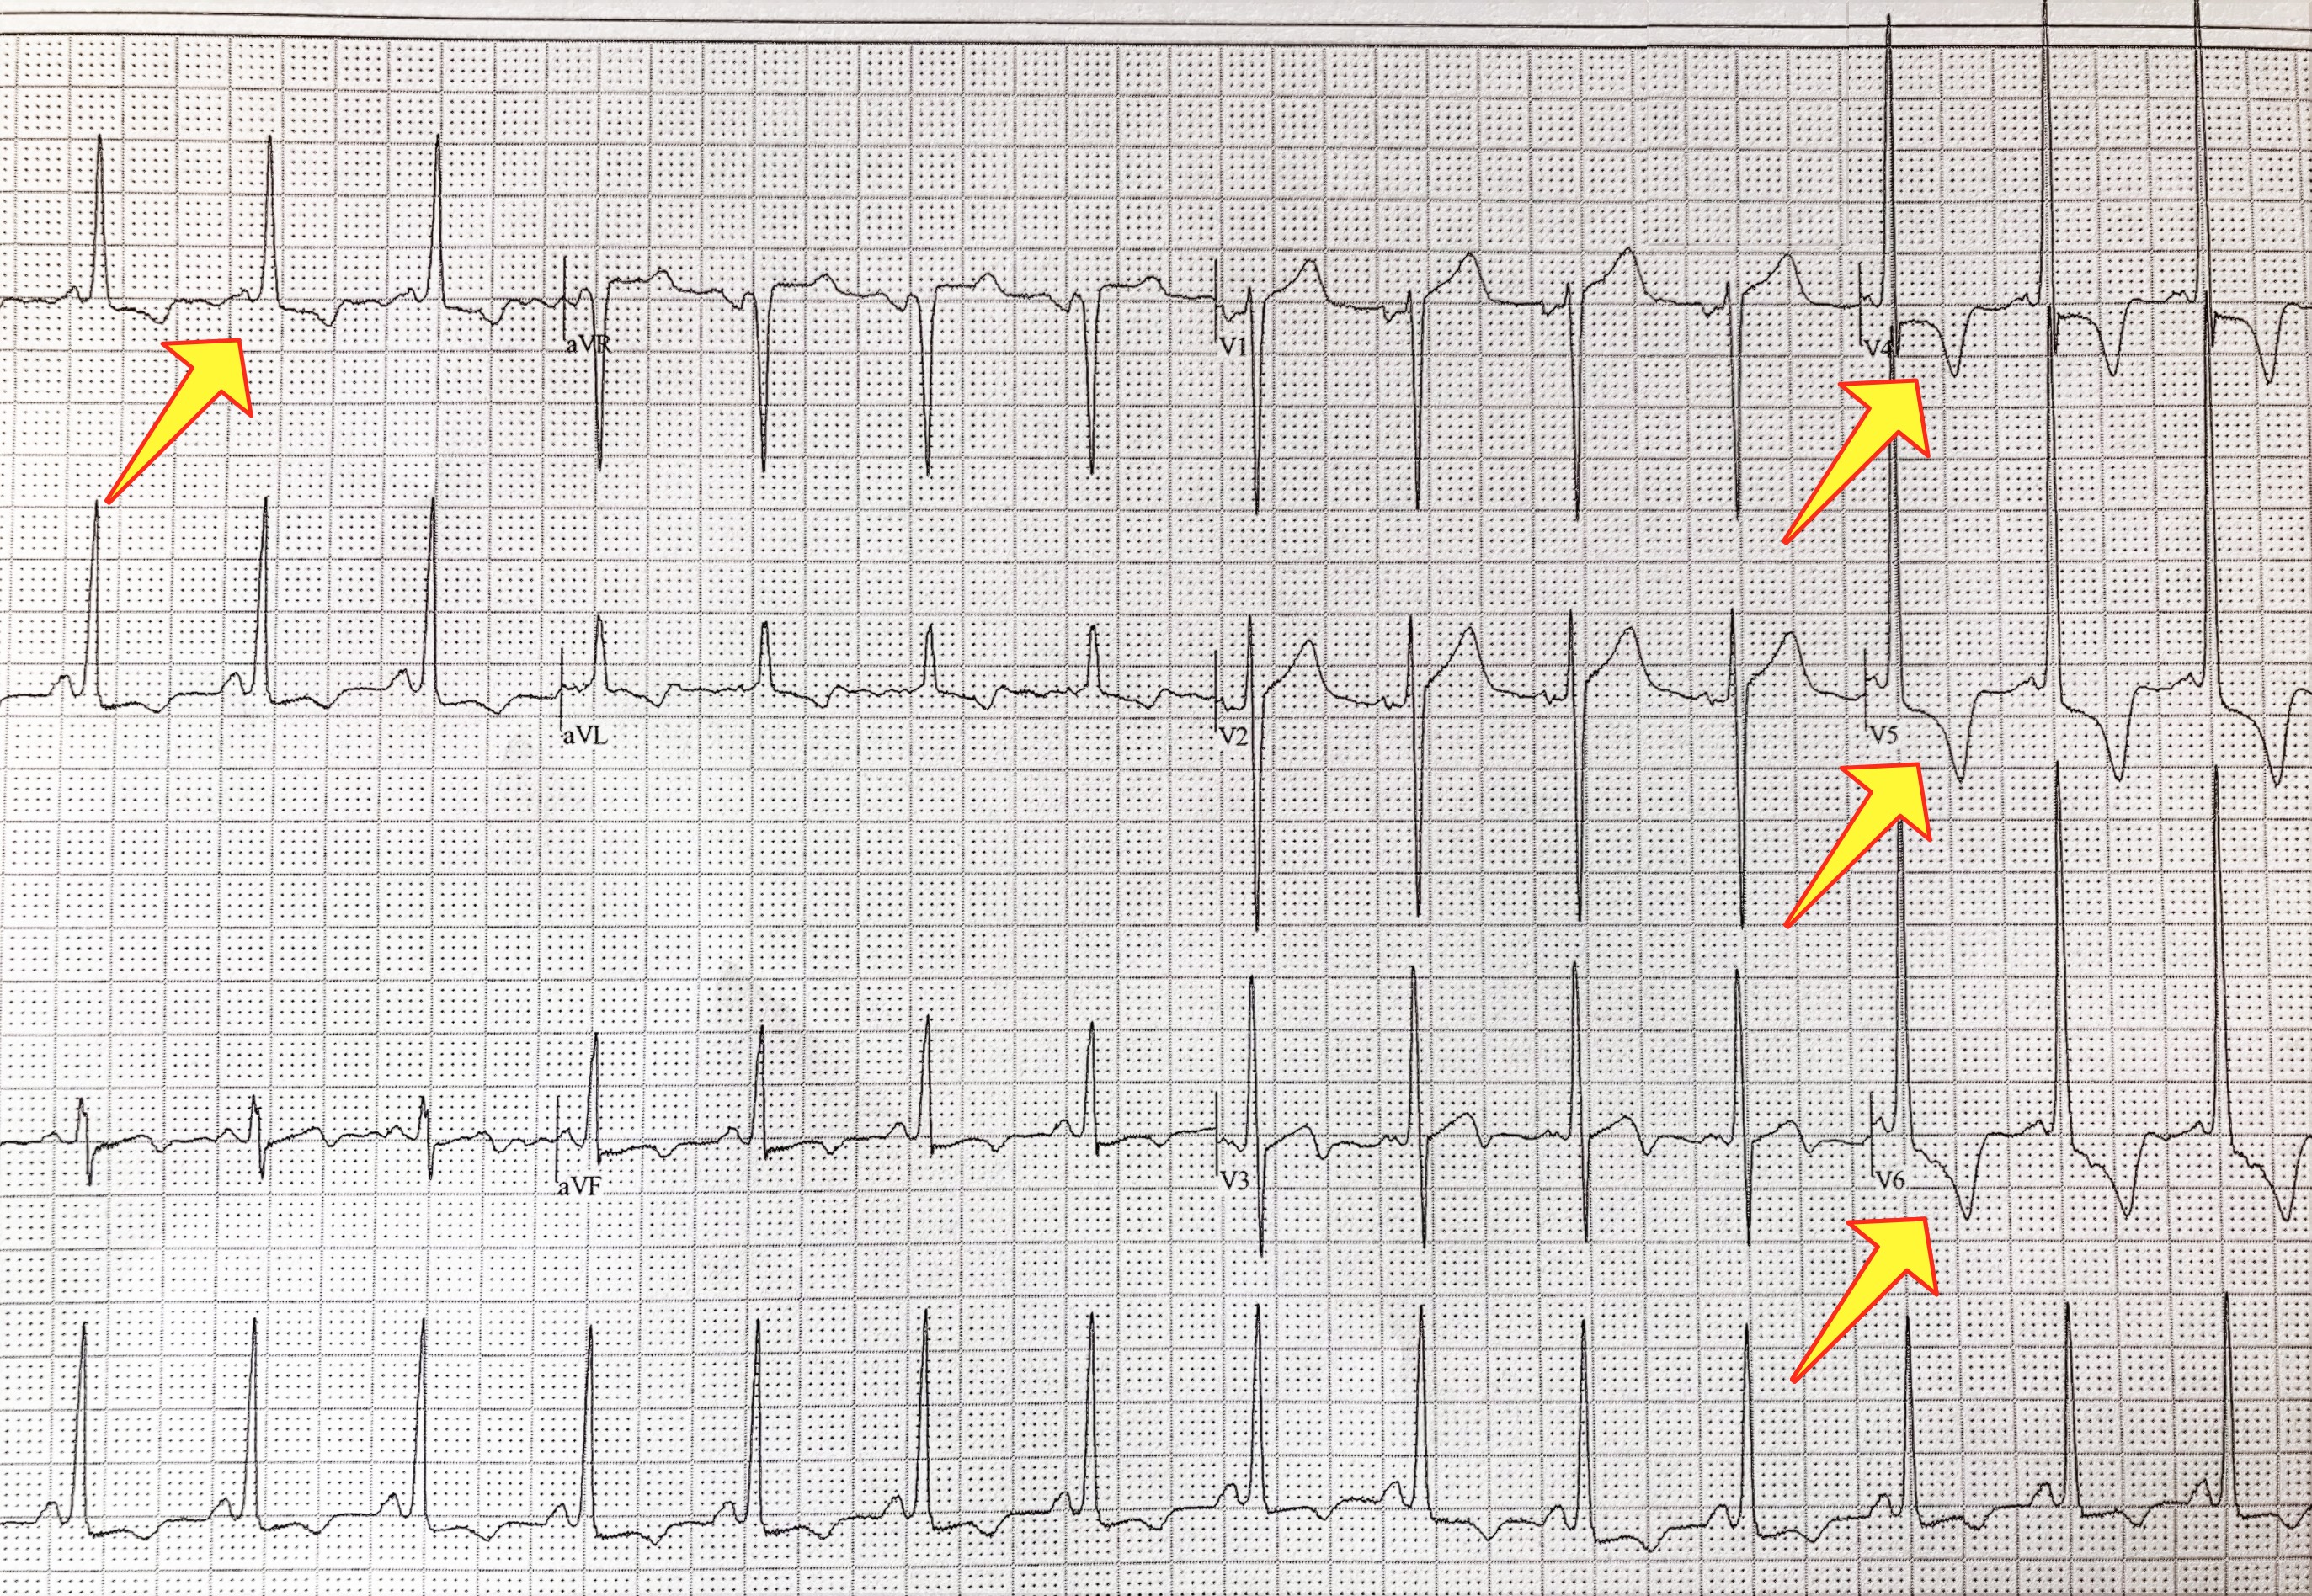

The echocardiogram is the test of choice to diagnose hypertrophic cardiomyopathy. Echo can identify the thickened muscle, measure it, and quantify the effect the abnormal muscle may be having on normal blood flow. The electrocardiogram of a patient with HCM is most often abnormal, and can help shed light on the condition; it is an excellent screening tool for HCM. This is one of the reasons why cardiologists obtain a baseline ECG on patients they see for the first time. In recent years, the cardiac MRI has emerged as one of the most important imaging tools for the heart because of its ability to create highly detailed pictures. A cardiac MRI can help diagnose HCM with great accuracy. It can detect even small amounts of thickened muscle that can be missed on echocardiography.

The technology to diagnose HCM with a blood test is in development and has not been fully developed in clinical practice. This is because only about 35 percent of HCM cases can be linked to a known gene that can be tested for. Also, it is still not clear how many cases of HCM appear from scratch, without a parent to inherit them from. Today, most of the screening for the disease is done by evaluating close relatives of the person affected. The echocardiogram and ECG are most often used for screening. Especially in younger people, screening may involve repetitive testing throughout life. If a causing gene is identified in a person suffering from HCM, then the same test can be used to diagnose other members of the family that could be affected.